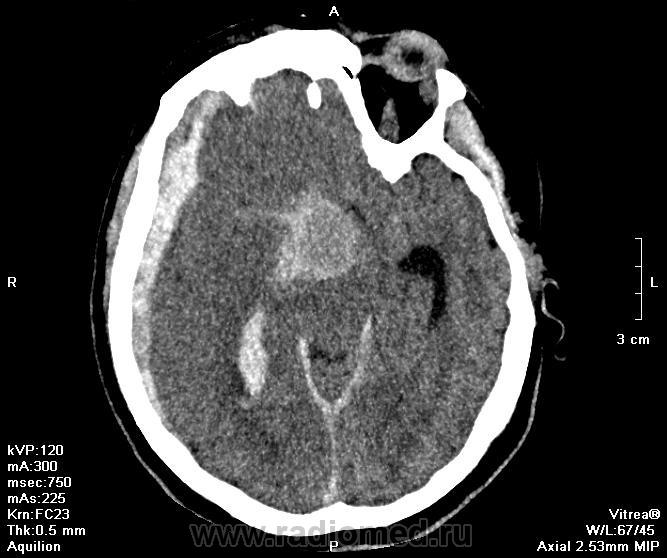

Аневризма ВСА

Субдуральное кровоизлияние. Прорыв крови в желудочковую систему.

Аневризма ВСА?

да, кстати, видимых повреждений нет, переломов костей черепа и ушибов мягких тканей на КТ нет.. т.е. субдуральная гематома не травматического генеза, что и вызывает вопрос о локализации аневризмы

четкие, ровные контуры - это она и есть. Меня интересует локализация, что дала субдуральное кровоизлияние, кровь во всех желудочках и не видно САК.

Вы сами ответили на свой вопрос. Чего только не бывает. Вероятнее всего супраклиноидный отдел. Для более точной локализации показана КТ-ангиография.

Как так - не видно САК. А затек по правому контуру,  разве не кровь в цистерне правой латеральной щели? А локализация - и передняя соединительная артерия может быть.